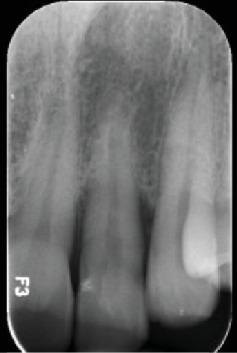

本病例报告讨论了成功处理与III期广泛性C级牙周炎相关的腭深发育沟。尽管先前进行了非手术牙周治疗,但病情进展迅速,需要进一步干预。综合评估显示广泛性牙周炎与局部牙齿相关的易感性因素,由于发育沟在重要的左上侧切牙。最初的非手术治疗包括刮除和根刨(SRP)以及全身抗生素。除发育凹槽部位外,其他部位均有显著改善。手术干预使用腭通道瓣牙成形术和根根成形术来消除剩余的袋和加强菌斑控制。手术成功地解决了问题,在6个月的随访中观察到软组织愈合,残余探探深度为3mm。本病例强调了与腭发育沟相关的挑战,作为牙周炎的局部加重因素。手术技术的使用,如牙成形术和皮瓣访问被证明是有效的管理牙周缺损相关的发育沟,展示了一个成功的结果在这个病人。

This case report discusses the successful management of a deep palatal developmental groove associated with Stage III generalized Grade C periodontitis. Despite prior nonsurgical periodontal therapy, the disease progressed rapidly, necessitating further intervention. A comprehensive evaluation revealed generalized periodontitis with localized tooth-related predisposing factor due to a developmental groove in the vital upper left lateral incisor. The initial nonsurgical treatment involved scaling and root planing (SRP) coupled with systemic antibiotics. Significant improvement was observed, except for the site with the developmental groove. Surgical intervention was performed using a palatal access flap odontoplasty and radiculoplasty to eliminate the remaining pocket and enhance plaque control. The procedure successfully resolved the condition, with soft tissue healing observed at the 6-month follow-up with a residual probing depth of 3 mm. This case highlights the challenges associated with palatal developmental grooves as localized aggravating factors in periodontitis. The use of surgical techniques like odontoplasty and flap access proved effective in managing periodontal defects associated with developmental grooves, showcasing a successful outcome in this patient.